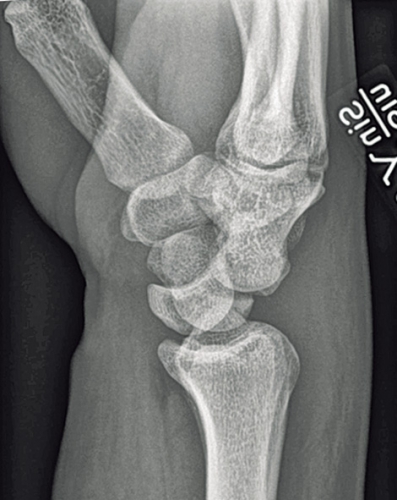

Observera att samtidiga ipsilaterala skador, t ex armbågsluxation, är vanliga. Akut karpaltunnelsyndrom förekommer i ungefär en tredjedel av fallen. Diagnosen ställs på röntgenbilden: Leta efter oordning bland karpalbenen och brutna Gilulas linjer! Observera att luxationen främst framträder på sidobilden, medan frontalbilden kan förefalla närmast normal. Man ska vara frikostig med datortomografi (DT), som kan påvisa mer ovanliga skademönster och synliggöra associerade karpala frakturer. Scaphoideum- och capitatum-frakturer är i detta sammanhang vanligast förekommande. DT kan också underlätta valet av snittföring. Observera att dessa skador alltid kräver öppen kirurgi, även om primär reposition lyckas och kontrollröntgen inte visar några frakturer. Enbart perkutan stiftfixation är aldrig till fyllest.

Skafolunära ligamentskador. När det gäller skafolunära ligamentskador är ligamentet mellan scaphoideum, trapezium och trapezoideum (STT), volara ligamentet mellan scaphoideum och capitatum (SC) och volara ligamentet mellan radius, scaphoideum och capitatum (RSC) viktiga s k sekundära stabilisatorer. När dessa ligament gradvis tänjs ut resulterar det i en karpal kollaps med statisk instabilitet som följd. På en röntgenbild i obelastat läge framträder då en volar flexionsfelställning av scaphoideum och en dorsal rotation av lunatum (DISI). Vanligtvis finner man då på röntgenbilden också ett »ring sign« i scaphoideum till följd av scaphoideums rotation.

Börja behandlingen med att direkt på akuten göra ett försök att reponera felställningen i lokalbedövning. Inled med ca 10 minuters kontinuerlig traktion [5]. Extendera sedan handleden under samtidigt kvarvarande mottryck över lunatum palmart, varefter handleden ska flekteras samtidigt som man även trycker direkt på capitatum dorsalt ifrån. Efter en lyckad sluten reposition är det ofta fördelaktigt att avvakta med definitiv kirurgi i 3–5 dygn för att svullnaden kring handleden ska hinna klinga av. Karpaltunneln kan dock behöva klyvas akut.